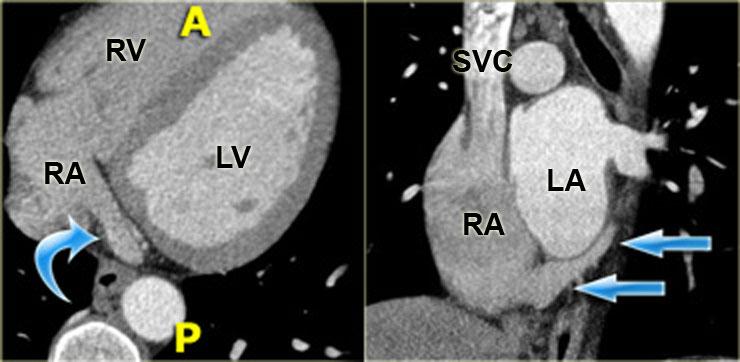

Tái tạo mặt cắt ngang (trái) và mặt cắt đứng dọc chếch (phải) cho thấy thất phải. Mũi tên xanh chỉ dải điều hòa. RA=nhĩ phải, RV=thất phải, LV=thất trái

Thất phải

Máu rời nhĩ phải và đi vào thất phải qua van ba lá.

Van này có ba lá van và ba cơ nhú, trong đó một phần bám vào vách liên thất (khác với các cơ nhú của van hai lá, vốn không bám vào vách).

Thất phải có hình dạng khác với thất trái: thất trái có hình trụ và buồng thất phải thực chất bao quanh nó.

Thất phải cũng có thành mỏng hơn với cấu trúc bè cơ nhiều hơn, đặc biệt ở vùng mỏm.

Dải điều hòa là một đặc điểm nhận dạng khác của thất phải.

Nó chạy từ vách liên thất đến thành bên của thất phải, và đóng vai trò quan trọng trong dẫn truyền điện sinh lý của thành tự do thất phải (mũi tên xanh).